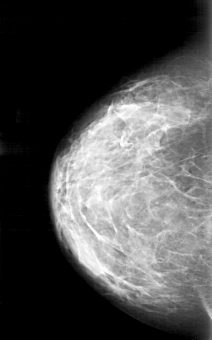

D_4171_1.RIGHT_CC

RIGHT_CC LINES 5086 PIXELS_PER_LINE 3166 BITS_PER_PIXEL 12 RESOLUTION 43.5 NON_OVERLAY